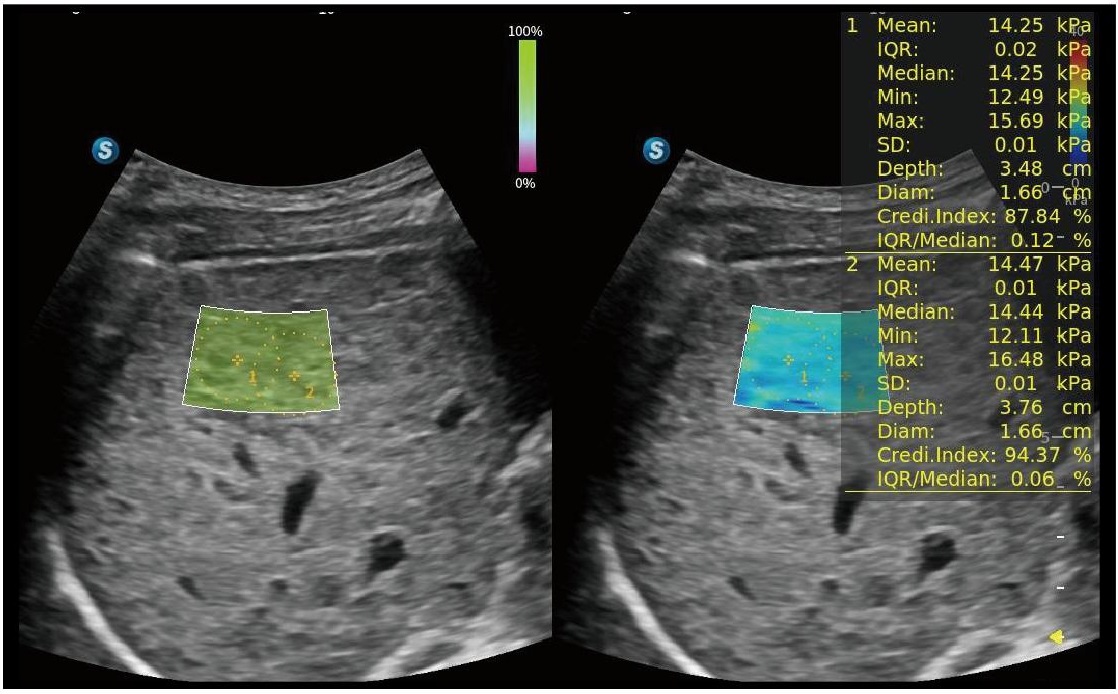

SWE

S-SWE (Shear Wave Elastography), karaciğer fibrozisinin kantitatif değerlendirmesini mümkün kılar ve klinik tanı güvenini artırmak için bir kalite haritası görüntüler.